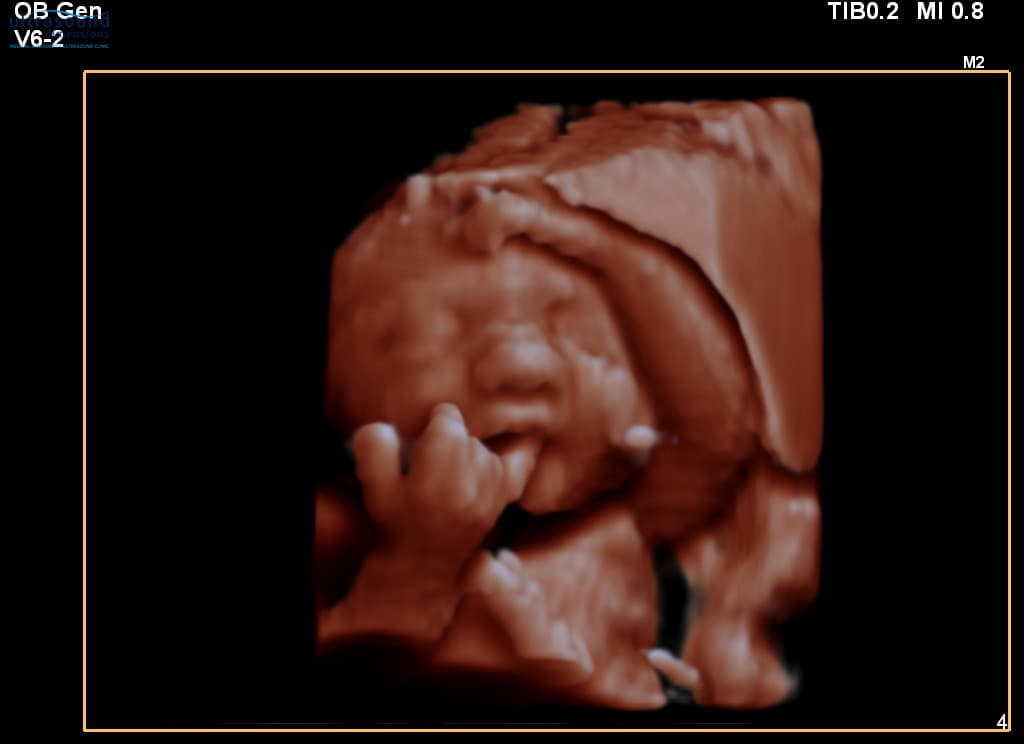

This adorable baby at 29 weeks is showing off their tiny hands during our Well Baby Scan (performed from 20-40 weeks).

Baby's Hands at 29 Weeks

At 29 weeks, your baby's hands are:

- Fully formed with all fingers and fingernails

- Able to grip and grasp

- Often held near the face

- Practising movements they'll use after birth